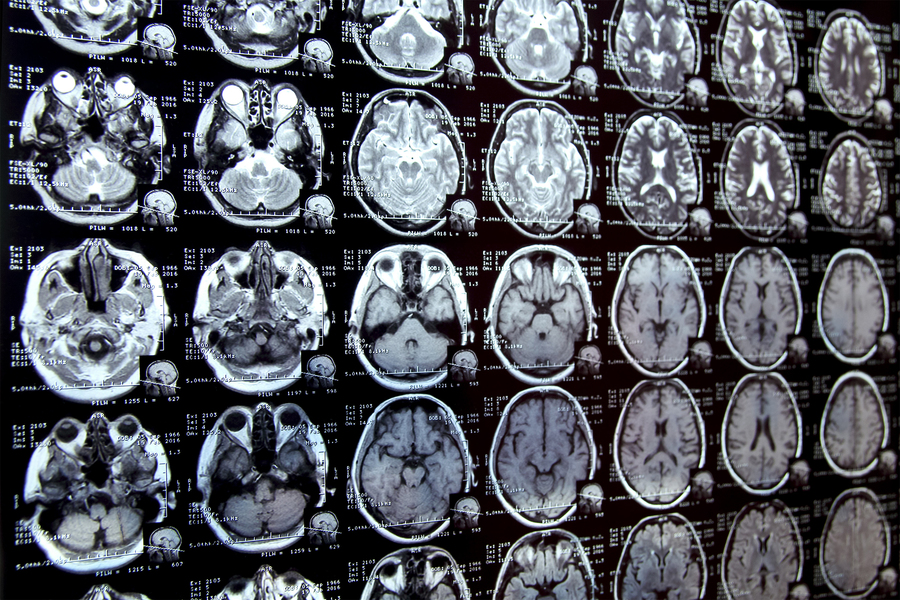

MIT researchers have developed a new AI-based tool that rapidly annotates areas of interest in medical images and can help in the study of new treatments or map disease progression (Credits: iStock).

Annotating regions of interest in medical images, a process known as segmentation, is often one of the first steps clinical researchers take when running a new study involving biomedical images.

For instance, to determine how the size of the brain’s hippocampus changes as patients age, the scientist first outlines each hippocampus in a series of brain scans. For many structures and image types, this is often a manual process that can be extremely time-consuming, especially if the regions being studied are challenging to delineate.